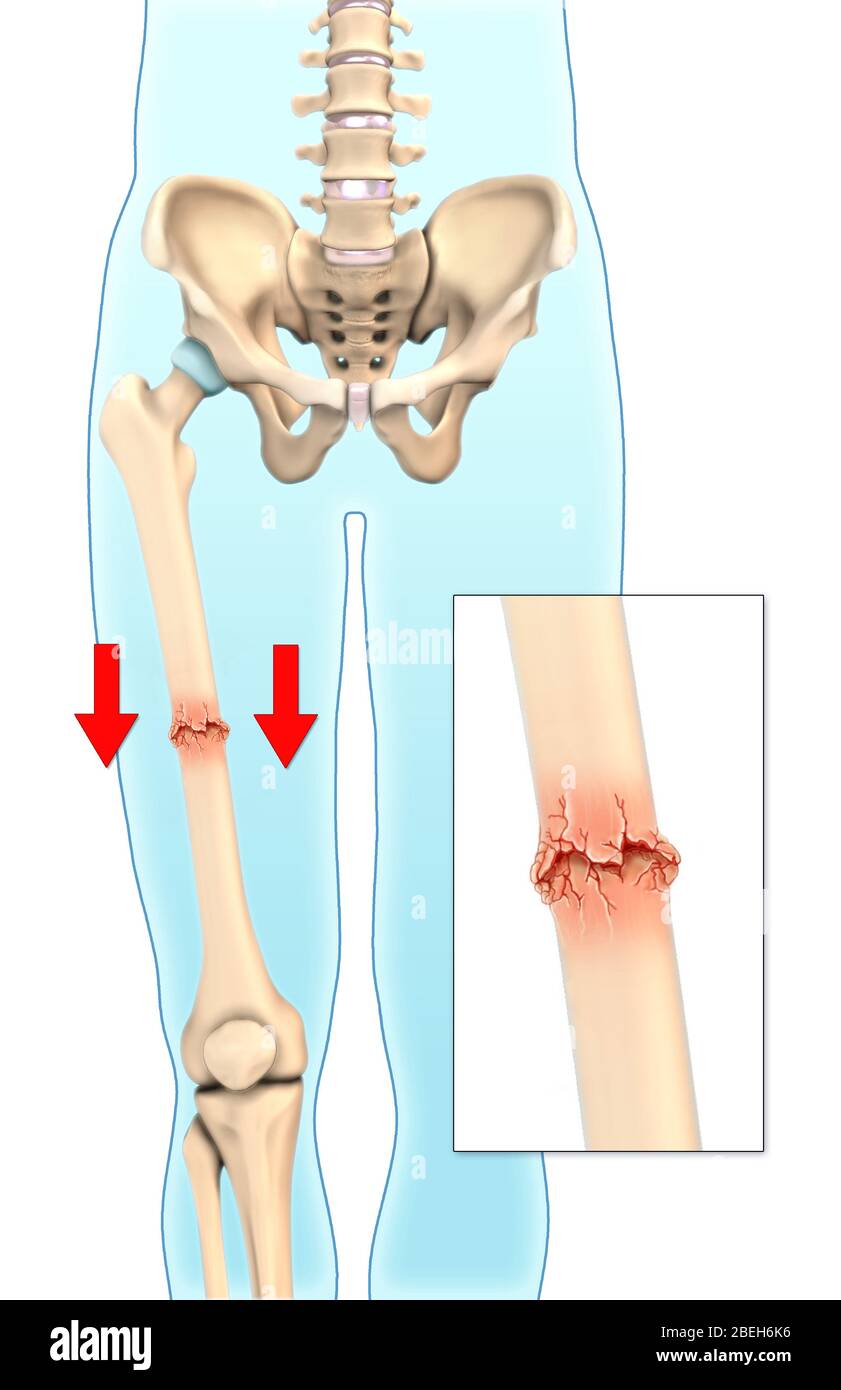

Fractures

are breaks or cracks in bones.

greenstick

Impacted

Closed

Open

Comminuted

Pott’s

Colles’

Stress